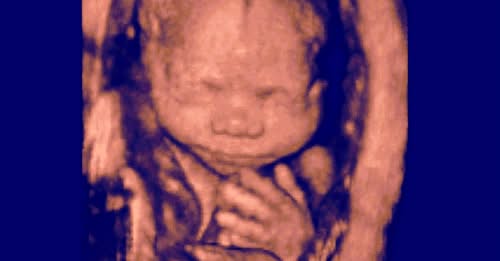

Despite Marie’s health struggles, a November 13 ultrasound revealed that Marie and her babies were doing quite well. At 22 weeks, Marie was measuring more like a pregnant woman at 35 weeks.

At 22 weeks, the tiny triplets didn’t have much of a chance. Not only was their gestational development delayed because they were triplets, but their little lungs hadn’t developed enough for them to breathe. As a nurse, Marie knew that ventilation efforts on underdeveloped lungs could explode the lungs, causing immediate death. Doctors told the parents that when born, the babies would not benefit from medical intervention.

The triplets were born in the early hours of November 15, each weighing between 360 to 450 grams, less than a pound each.

Despite the deep sorrow of having to let their children go, the parents were nonetheless taken aback by how perfectly formed their little children were, with perfect little noses, tiny toes, dainty fingers and finger nails, and most of all, beautifully lovable faces.